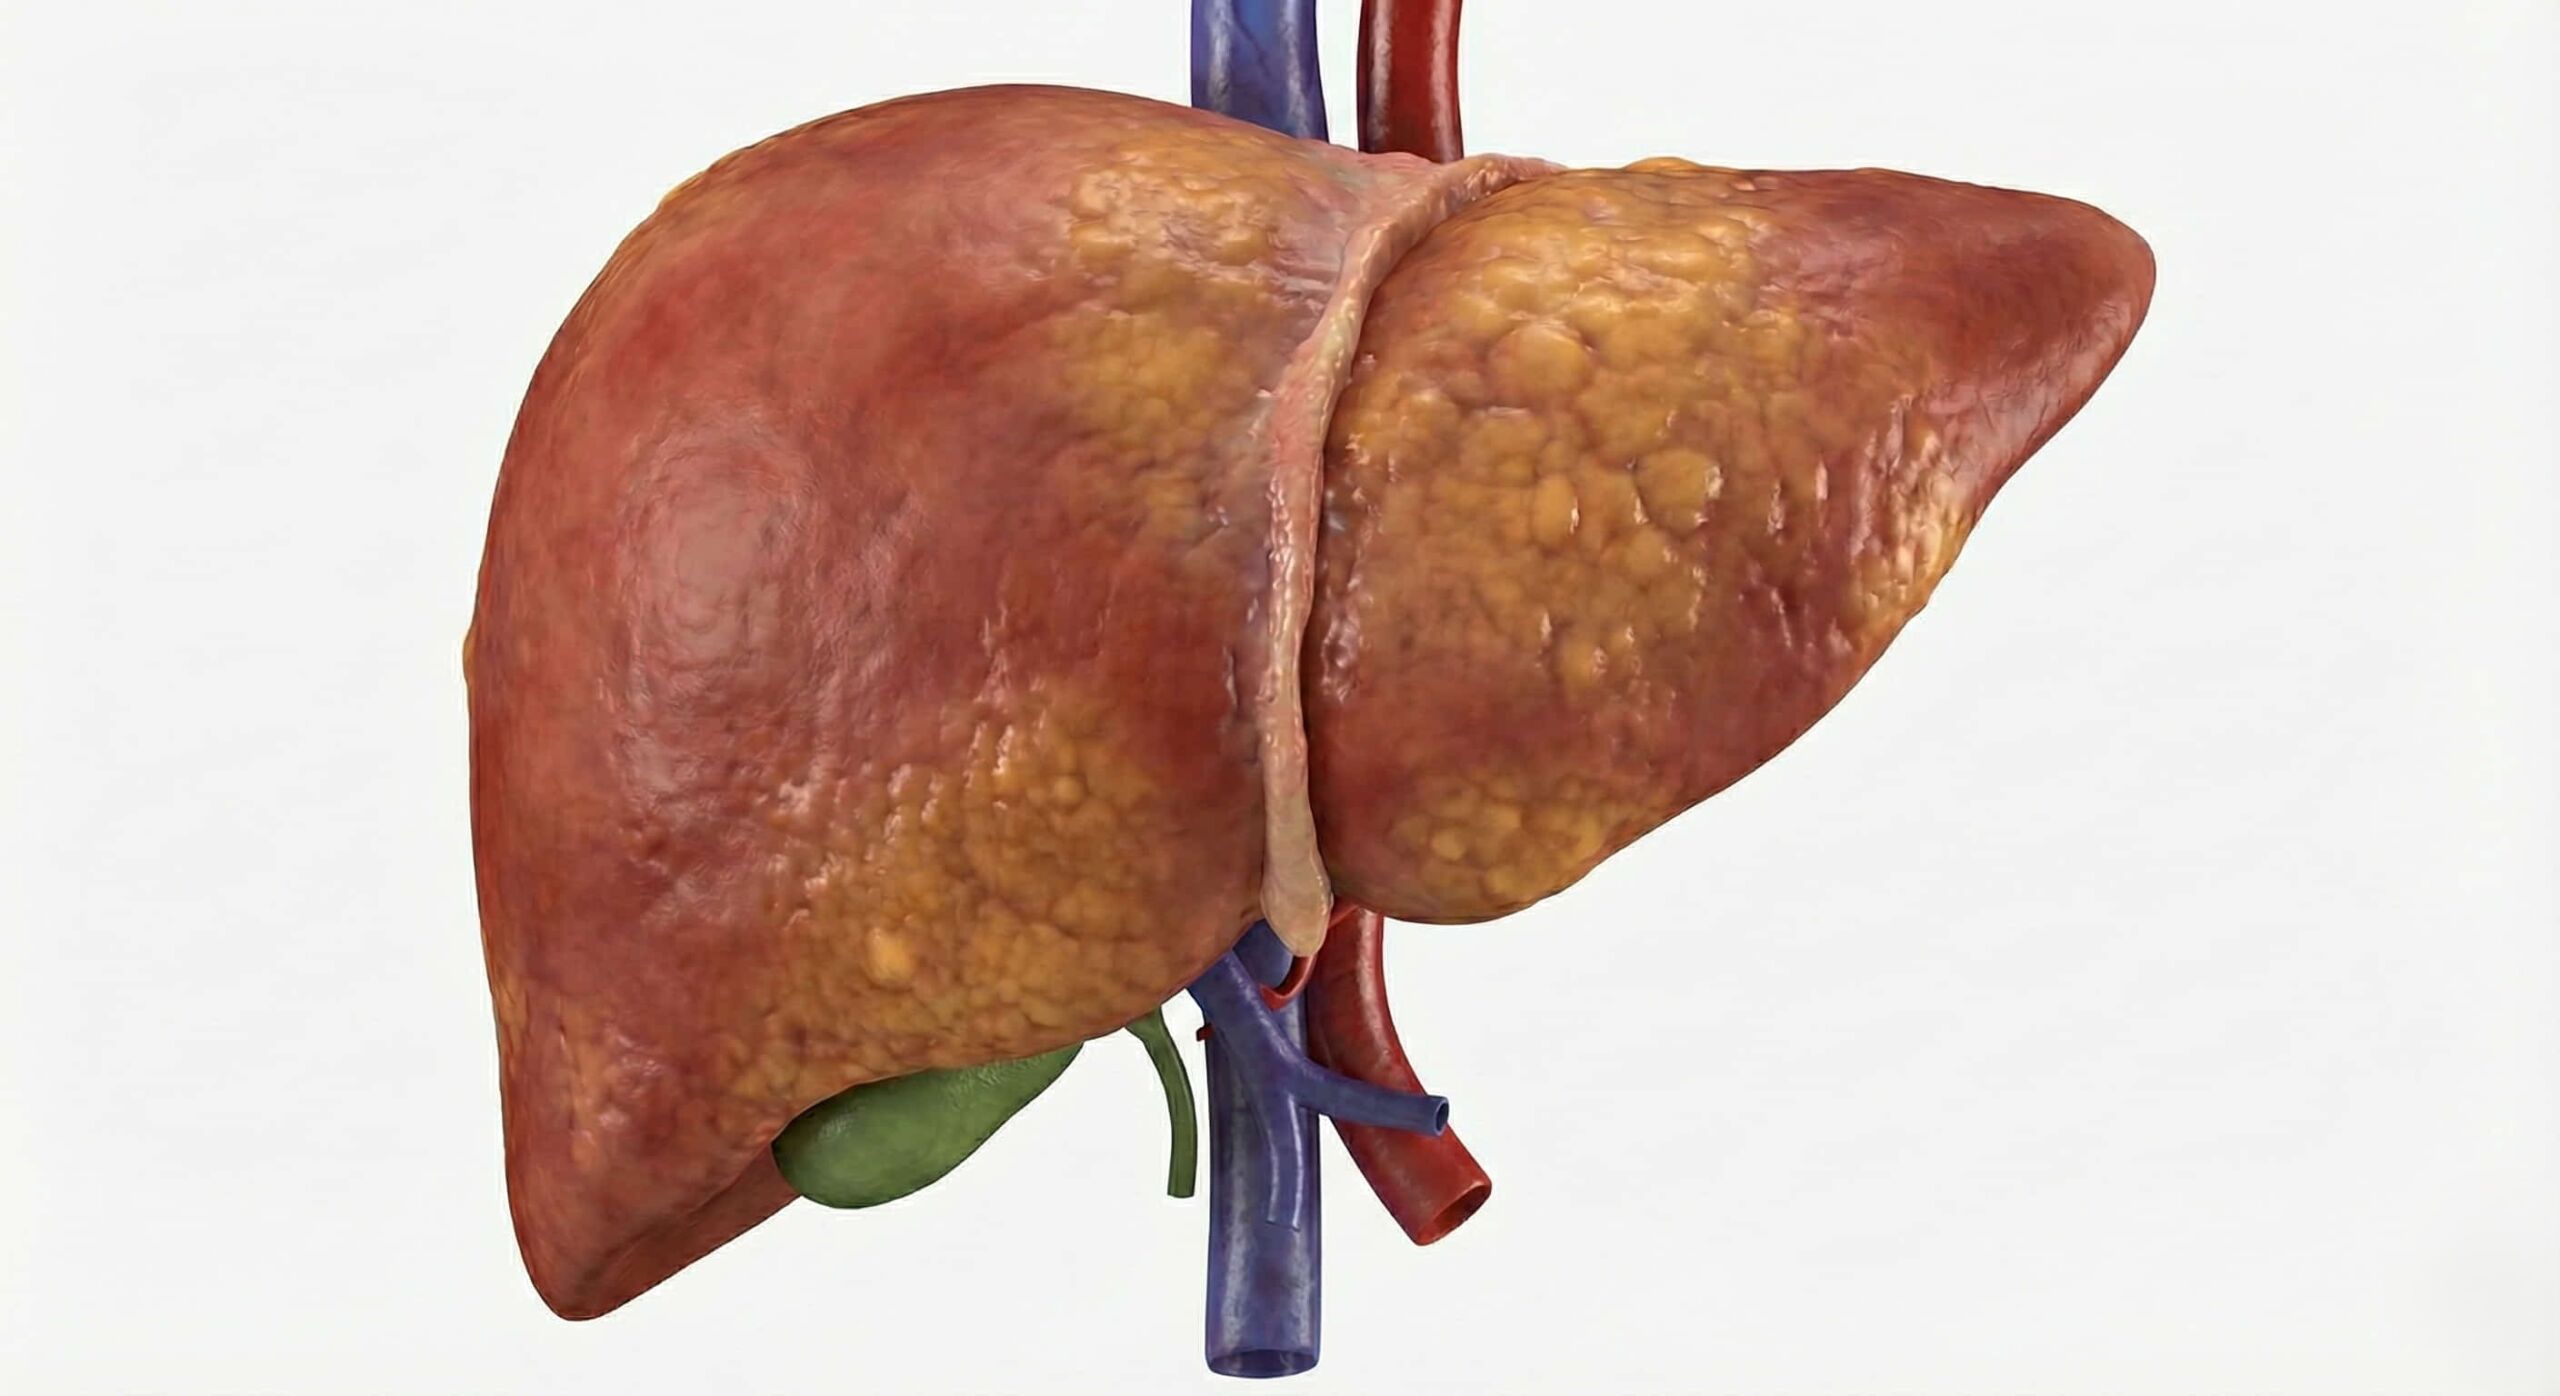

🩺 What is a Transhepatic Venous Catheter?

This procedure involves placing a catheter directly through the liver and into one of the hepatic veins, which then drains into the Inferior Vena Cava (the body’s largest vein). Because of the complexity of the anatomy, this “extreme access” procedure is only performed by the most experienced interventional radiologists in India.

The liver is a large, resilient organ. The catheter occupies a very tiny path through the liver tissue, which does not affect your overall liver function. The site heals quickly around the catheter.

The transhepatic route is considered a long-term durable access. Because the hepatic veins (liver veins) are large and have high blood flow, they are much less likely to "scar down" or block up as quickly as the smaller veins in the arms or neck. For many patients with Central Venous Occlusive Disease, this becomes their stable, permanent lifeline for years.